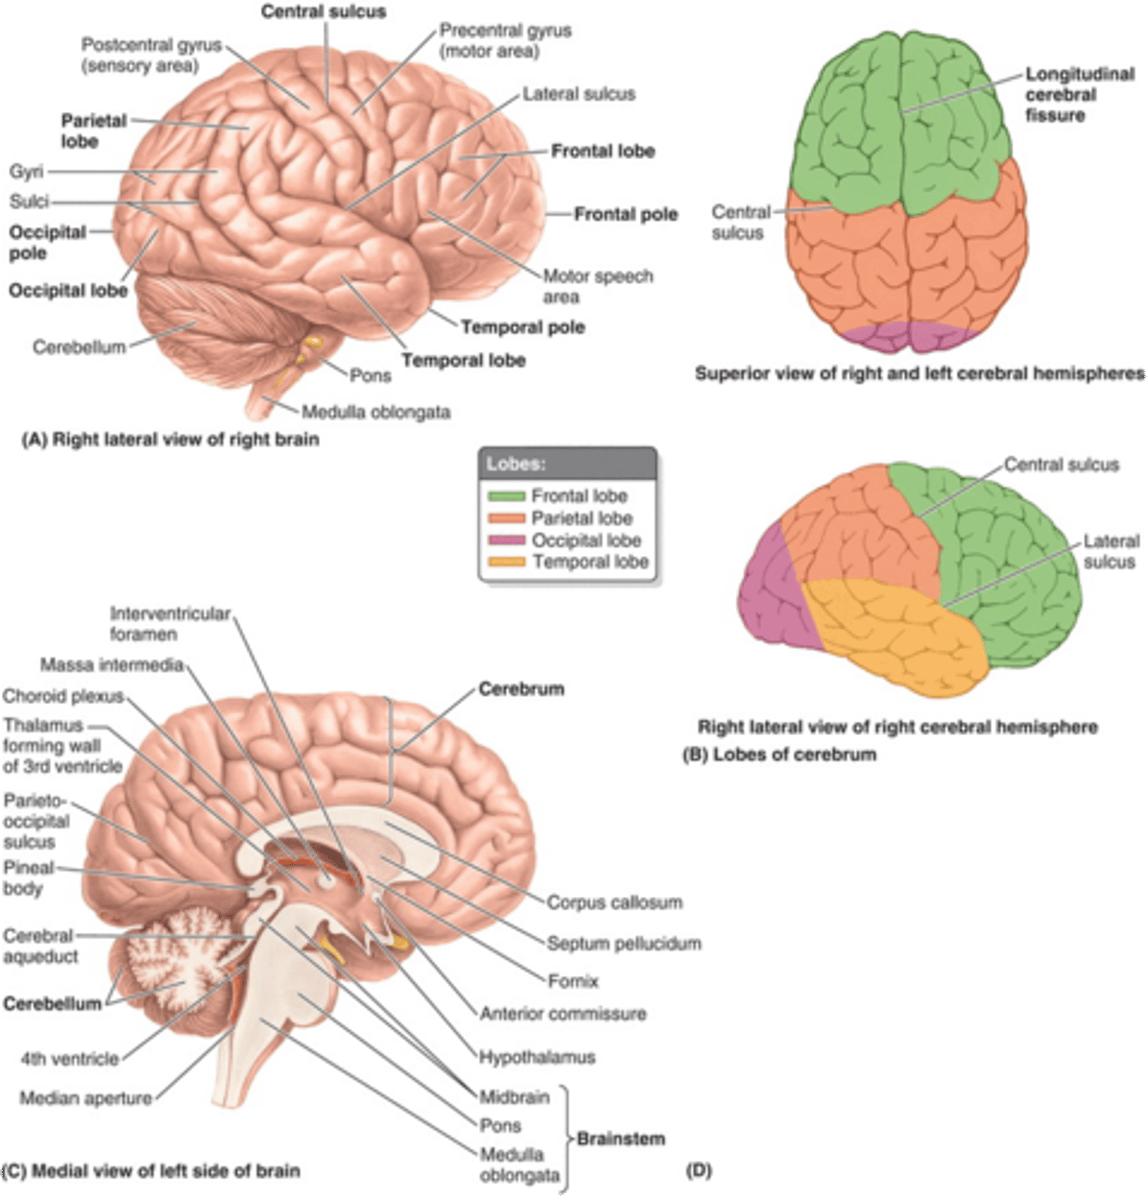

what are the 3 regions of the brain?

1. cerebrum (cerebral hemispheres)

2. brainstem

3. cerebellum

what are the 4 main lobes of the cerebrum?

FPOT

1. frontal

2. parietal

3. temporal

4. occipital

what lobe of the cerebrum is involved with motor and personality?

FPOT

frontal

what lobe of the cerebrum is involved with sensory?

FPOT

parietal

what lobe of the cerebrum is involved in hearing and memory?

FPOT

temporal

what lobe of the cerebrum is involved in vision?

FPOT

occipital

which sulcus separates the cerebral hemispheres?

longitudinal fissure

which sulcus divides the frontal lobe from the parietal lobe and divides the precentral and postcentral gyrus?

central sulcus

which sulcus divides the parietal lobe from the temporal lobe?

lateral (sylvian) sulcus/fissure

which sulcus separates the parietal lobe from the occipital lobe?

parieto-occipital sulcus

which gyrus is the primary motor complex?

precentral gyrus

which gyrus is the primary somatosensory complex?

postcentral gyrus